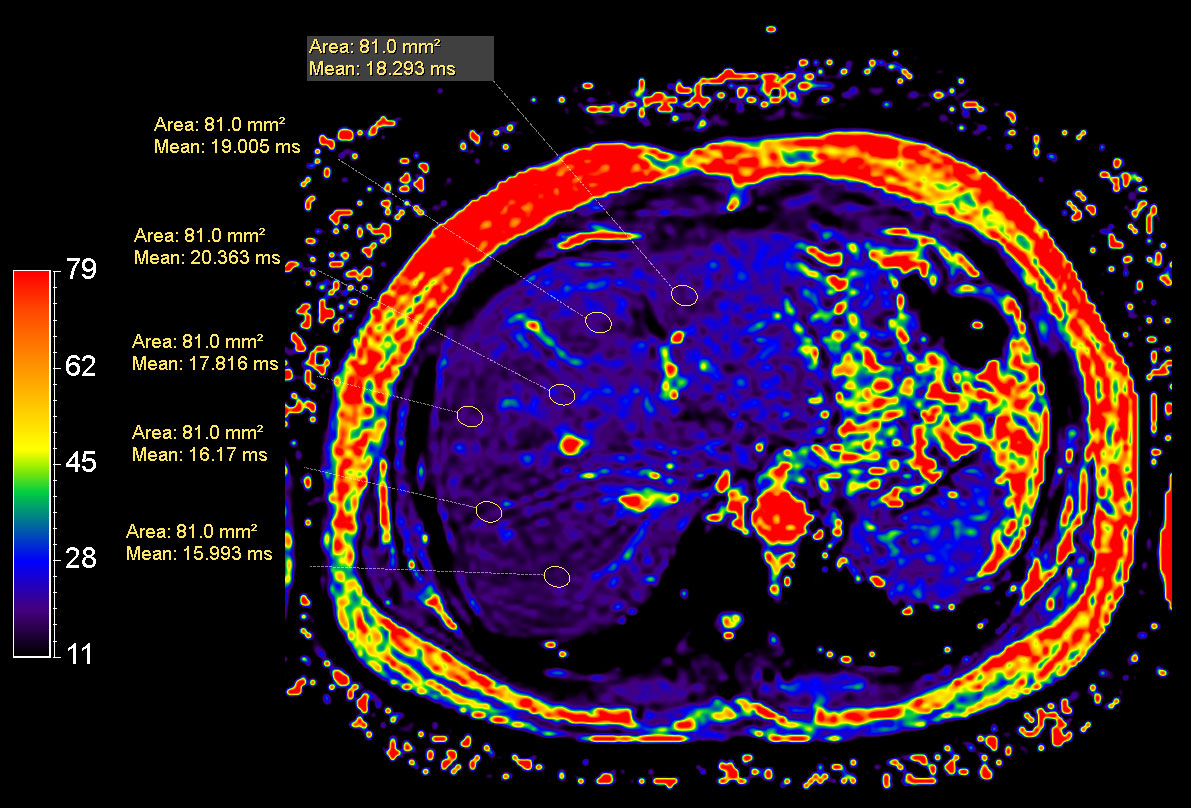

mDIXON Quant (Fat Fraction)

mDIXON Quant (T2 star)